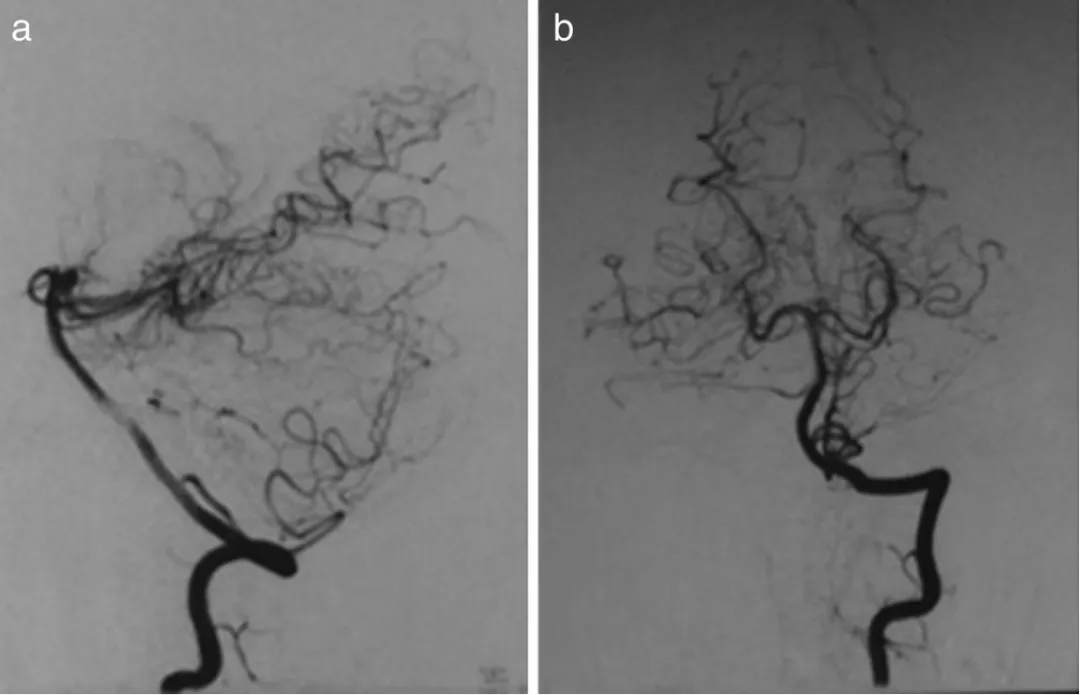

第7天血管造影确诊为创伤后动脉瘤合并动静脉瘘,异常静脉直接从动脉瘤顶部引流至颈内静脉,形成血管"短路"。

图a、b、c显示第7天右椎动脉造影,可见动脉瘤位于左小脑前下动脉近端

第14天复查造影显示动脉瘤明显增大,破裂风险显著增加

图d、e显示第14天右椎动脉造影,动脉瘤扩大,动静脉瘘更加明显